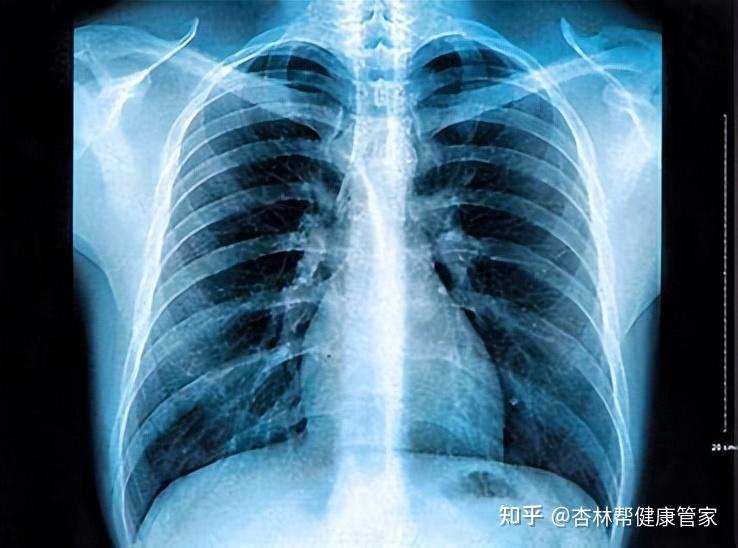

血尿肌紅蛋白增高血清心肌酶增高有助于急性心肌梗死的診斷腦腔及心包腔穿刺液的化驗及細胞學檢查器械檢查胸腔內臟器官疾患需借助有關的器械檢查確定診斷胸部X線檢查在現代胸部疾患的診斷占有重要地位,常規X線檢查可顯示計多胸部病變的影像,作為病變的診斷依據如肺炎,肺結核,肺梗死,肺癌,胸膜病變。

1體檢請先預約安排體檢前一天忌酒,限高脂高蛋白飲食,避免使用對肝腎功能有影響的藥物2檢查前三五日飲食宜清淡,勿食豬肝豬血等含血性之食物,檢查前一日晚上十二點以后,請完全禁食包括飲水3做X線檢查時,宜穿棉布內衣,勿穿帶有金屬鈕扣的衣服文胸請摘去項鏈手機鋼筆鑰匙等金屬物品懷孕及有可能。